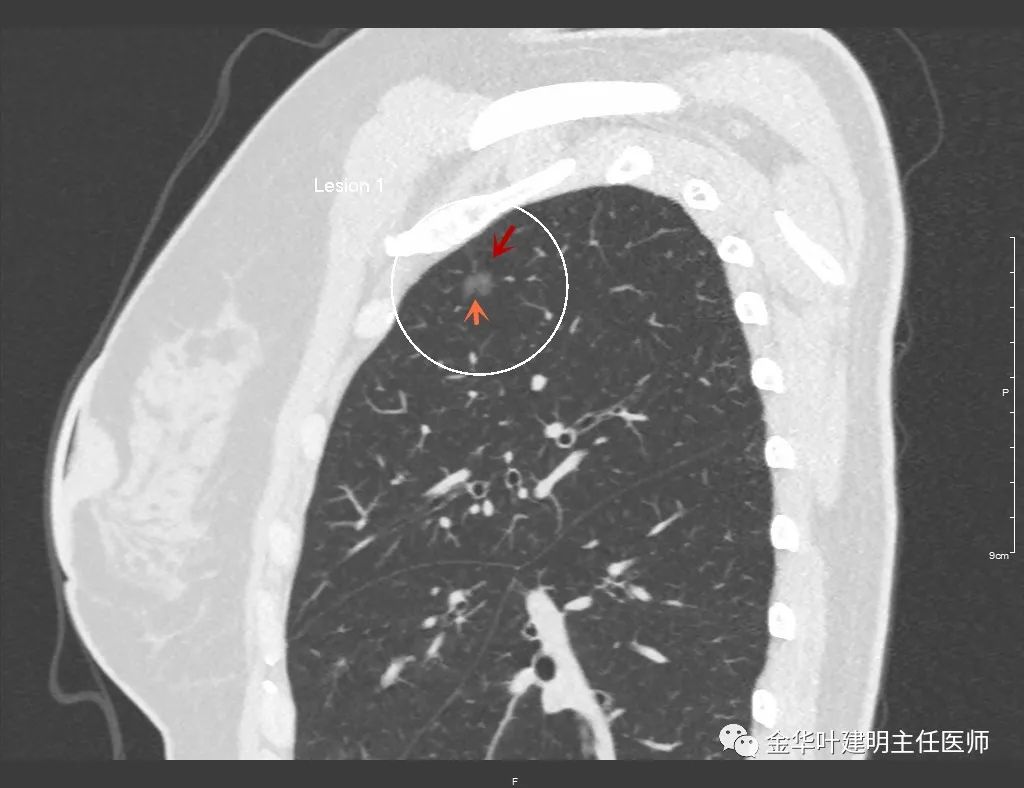

纵向看病灶密度稍不均,桔色箭头示病灶有浅切迹致略分叶

上图的蓝色箭头示尖段的前亚段支气管,而紫色箭头示尖段的尖亚段支气管开口处及少许向头侧走行的区域